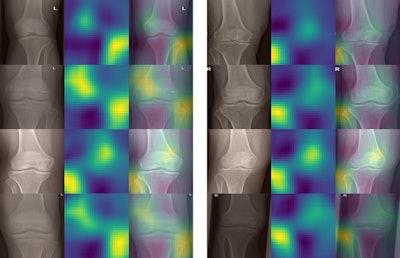

To understand how the network made its decisions from the x-rays, the researchers applied occlusion sensitivity maps for rough estimates of which parts of the knee x-ray contributed to a given decision. As expected, the fibula seemed to be the most important part for determining the anatomical side of the x-ray, the authors wrote.

Unexpectedly, in many images a second hot spot was visible on the opposite side of the fibula and above the intercondylar area. This indicates the model seemed to take into consideration the slant of the lower end of the femur, which seems also to be a rather good indication of whether the knee is a left or right one, the researchers wrote.

Occlusion sensitivity maps for randomly selected images from the internal validation cohort (left column) and external validation cohort (right column). In each row, first the cropped, original image is shown, then the occlusion sensitivity map, and finally an overlay of both. In general, two hot spots are visible, which correspond to the region that is most important for the network for its decision: the fibula as well as the lower end of the femur opposite to the fibula. Image courtesy of Scientific Reports.Ultimately, the authors restricted the study to knee radiographs but suggested they have little doubt that similar networks can be developed for identifying anatomical sides for other body parts, such as the chest, abdomen, spine, and upper and lower extremities.